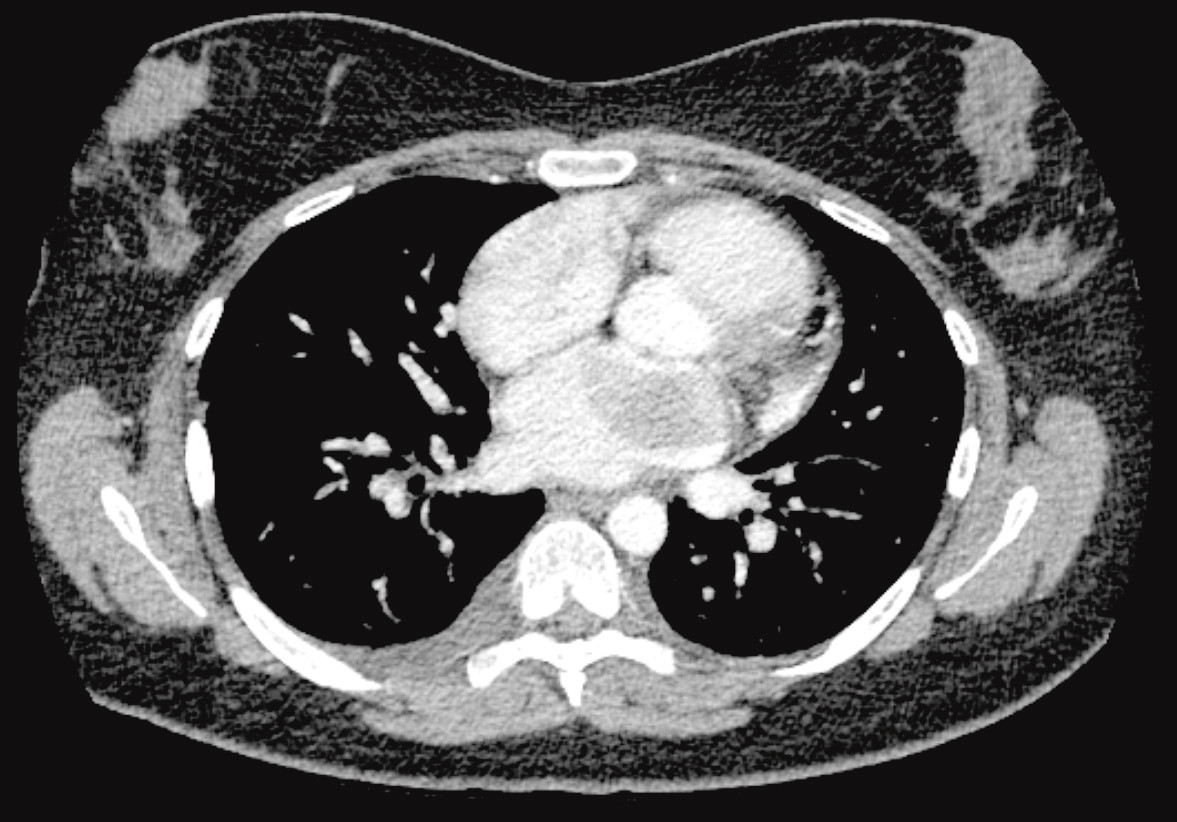

Bildediagnostisk utredning med røntgen thorax (figur 1) viste funn som kunne passe med stuvning. Pasienten var ung uten kjent hjertesykdom, og man vurderte derfor stuvning som mindre sannsynlig. Ut ifra røntgenbildene ble det reist mistanke om luftveisinfeksjon eller mulig interstitiell lungesykdom, differensialdiagnostisk stuvning. CT thorax (figur 2) avdekket en oppfylning i venstre atrium og bekreftet tegn til stuvning. Ekkokardiografi viste en stor ekkohomogen, velavgrenset og stilket tumor utgående fra atrieseptum, som nær utfylte venstre atrium og i diastole obstruerte mitralostiet. Funnet ga mistanke om myksom. Hun hadde sikker leiebetinget dyspné ved undersøkelsen.